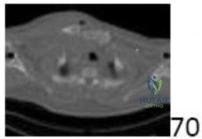

A 45-year-old male presents with weakness in his intrinsic hand muscles and numbness in his small and ring fingers. Froment's sign is positive. Intraoperative exploration of the ulnar nerve at the elbow reveals compression by an anomalous muscle bridging the medial epicondyle and the olecranon. What is the name of this anatomical structure?